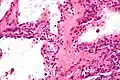

![]() | |

Micrograph showing a pancreatic serous cystadenoma. H&E stain. | |

Pathologists classify serous cystic neoplasms into two broad groups. Those that are benign, that have not spread to other organs, are designated "serous cystadenoma".[5] Serous cystadenomas can be further sub-typed into microcystic, oligocystic (or macrocystic), solid, mixed serous-endocrine neoplasm, and VHL-associated serous cystic neoplasm. This latter classification scheme is useful because it highlights the range of appearances and the clinical associations of these neoplasms. Serous cystic neoplasms that have spread ("metastasized") to another organ are considered malignant and are designated "serous cystadenocarcinoma".

Pathology